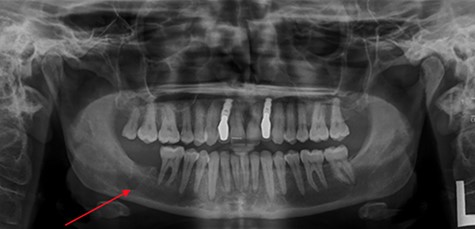

OPG taken on admission to RDH. Note: LR7 has been extracted and there is a patch of radiolucency inferior to LR7/8.